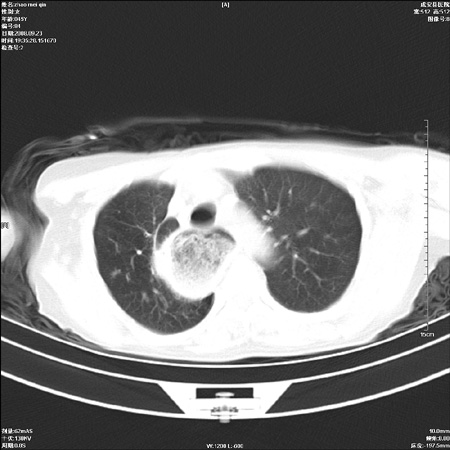

标题: CT15861:女 60 外伤后1小时 胸疼 [打印本页]

标题: CT15861:女 60 外伤后1小时 胸疼

外伤后1小时 胸疼 是外伤后引起的吗?

食道扩张明显下端逐渐变窄,倒像贲门失迟缓

食道扩张明显下端逐渐变窄,大量食物存留,象贲门失迟缓症。

非外伤性改变,典型的贲门失迟缓症